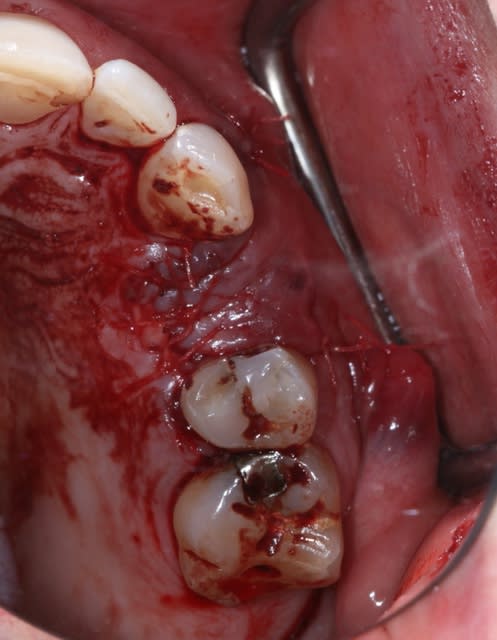

-fracture 25

-infection

-extraction (oups la ccm sur implant s'est descellée...)

-pas de pose d'implant car destruction de la paroi vestibulaire sur près de 5 mm

-pas de lambeau mais décollement vestibulaire muco-périosté à travers l'alvéole d'extraction et interposition d'une membrane de Collagen AT entre l'os et le périoste

-comblement BioOs et recouvrement avec même type de membrane

-conjonctif pédiculé tracté (comme j'ai pu) pour fermeture du site d'"extraction.